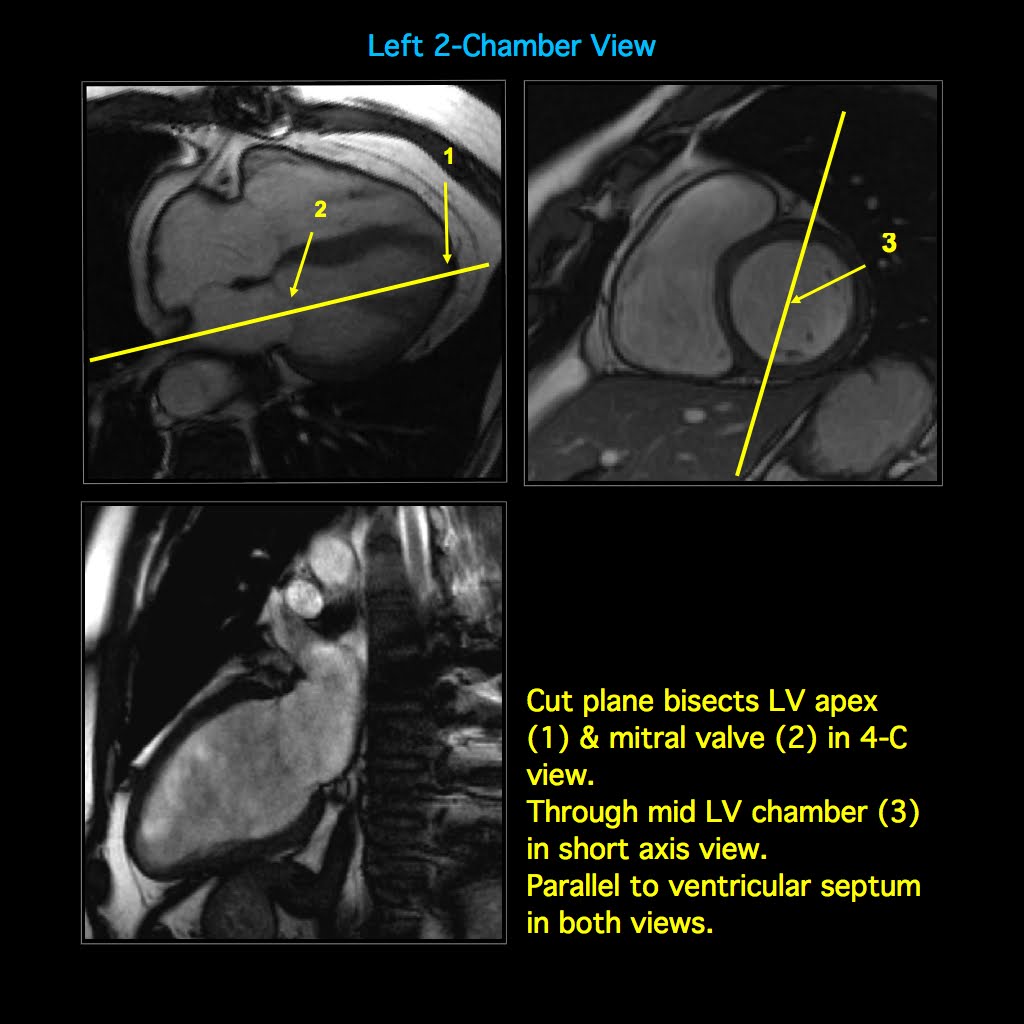

CARDIAC MRI